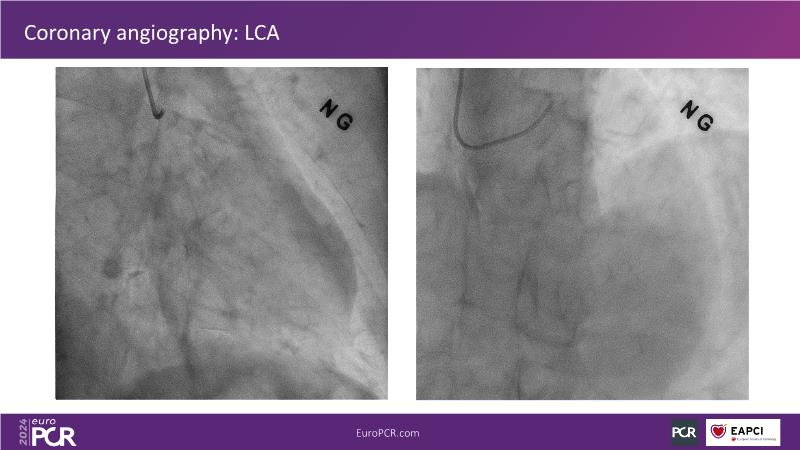

From innovation to reality: the impact of Cre8 EVO technology on complex PCI

This session is a good opportunity to delve into the contemporary technical and clinical complexities surrounding complex PCIs in challenging patient cases. Explore the necessary tools and treatment strategies to enhance peri-procedural and long-term clinical outcomes, and follow discussions on the unique technologies of Cre8 EVO in complex PCI scenarios.